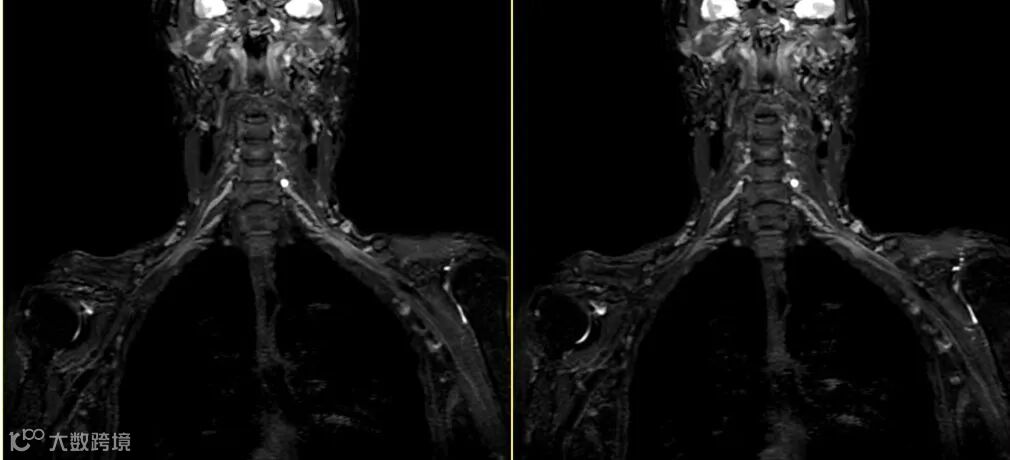

在对有金属植入物的扫描中,采用高带宽可有效改善其磁敏感伪影导致的变形失真,如高带宽+STIR的方式。

实际扫描中会涉及到很多改善磁敏感伪影和运动伪影的技术,在应用这些技术时不宜采用过窄的带宽。如在使用抗运动伪影的螺旋桨/风车/刀锋序列来改善其伪影时建议采用高带宽。